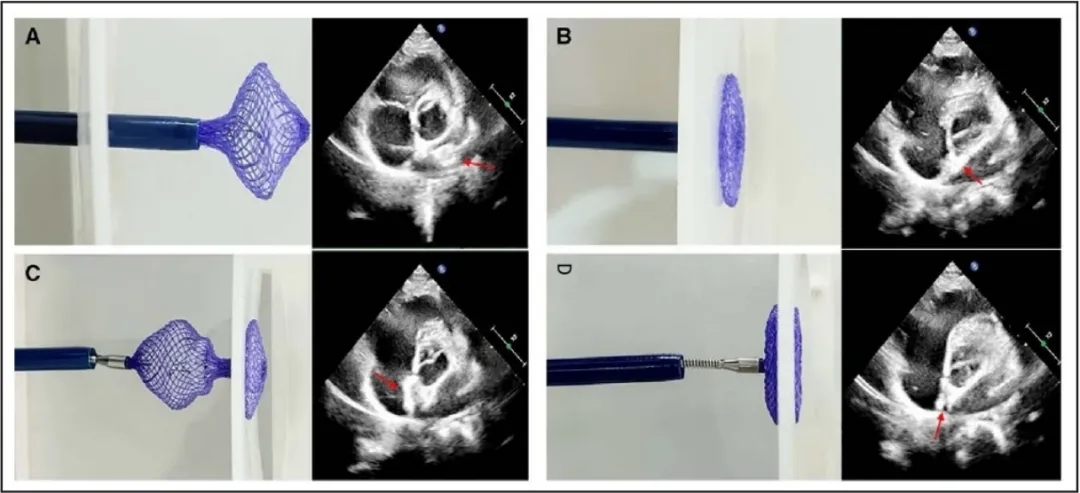

图2.新型生物可降解卵圆孔未闭封堵器

该新型生物可降解封堵器主要由封堵器骨架、阻流膜、成型环(黄色箭头)和成型线(白色箭头)组成。A,未锁定时封堵器形态。B,锁定后封堵器形态。

在局部麻醉后,试验组在经胸超声(TTE)引导下进行卵圆孔未闭(PFO)封堵术。首先将一根0.035英寸的导丝引入下腔静脉,随后推进至右心房。28在持续的超声引导下,导丝通过PFO进入左心房。接着沿导丝将输送鞘推进至左心房,并在超声引导下通过鞘管释放封堵器。在释放封堵器时,先展开左盘(图3)。若观察到伞盘形态不佳,则轻拉成型线使左盘成型。然后轻轻回撤整个输送系统,使左盘贴合房间隔。接下来,固定钢缆,后撤输送鞘管,展开右盘。为确保右盘成型良好,应在向前抵住输送鞘管的同时向后轻轻牵拉成型线,从而产生相反的力,使封堵器形成“双伞”结构。如果封堵器位置不理想,则将其回收进输送鞘中,并在超声引导下重新展开。一旦封堵器到形态位置良好,进一步牵拉成型线,将成型环锁定在封堵器外部。在超声引导下通过轻轻推拉钢缆进行牵拉试验,以评估封堵器是否锁定。如果封堵器成功锁定,则PFO封堵器整体会随钢缆移动;若封堵器未成功锁定,则右伞盘被牵拉变形,表明需要重新锁定。确认封堵器锁定成功后,剪断并抽出成型线,旋拧钢缆释放封堵器。

图3.封堵器锁定成型过程示意图

左,器械演示。右,术中TTE影像。A,新型生物可降解封堵器(红色箭头)从输送鞘中展开左盘后呈灯笼状。B,当轻轻牵拉连接在封堵器左盘的成型线时(红色箭头),新型生物可降解封堵器左盘从灯笼状逐渐变化成盘状。C,新型生物可降解封堵器的右盘(红色箭头)从输送鞘中释放后呈灯笼状。D,锁定后整个封堵器形成双伞结构(红色箭头)。